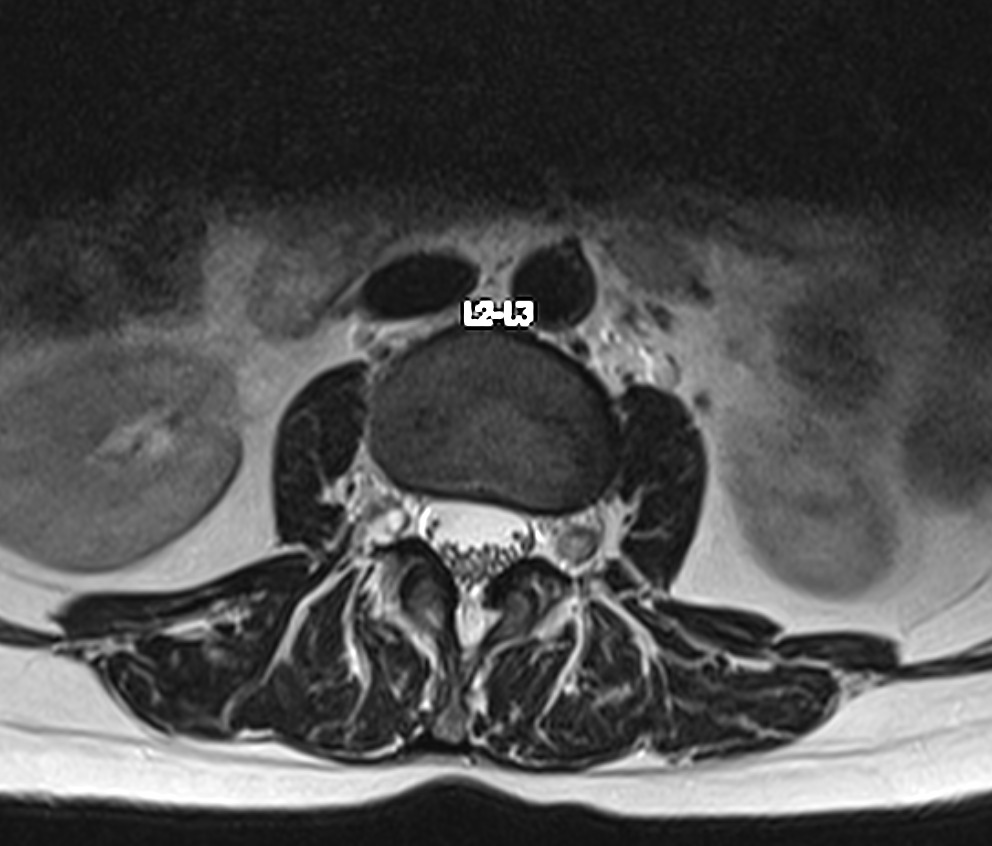

Resonancia Magnética de columna lumbar

“QUISTES PERINEURALES”

Los quistes perineurales son quistes llenos de líquido cefalorraquídeo en las raíces nerviosas, localizados principalmente en la zona sacra de la columna vertebral, aunque pueden encontrarse en cualquier sección de la columna vertebral; pueden causar una radiculopatía progresivamente dolorosa. Las mujeres se ven afectadas con mayor frecuencia que los hombres. Los pacientes con quistes perineurales presentan dolor en la zona de los nervios afectados por el quiste, debilidad muscular, dificultad para sentarse durante periodos prolongados, pérdida de la sensibilidad, pérdida de reflejos, dolor al estornudar o toser, inflamación en la zona sacra, parestesias, dolor de cabeza, ciática, y disfunción intestinal, de vejiga y sexual.

El diagnóstico se basa en la resonancia magnética.